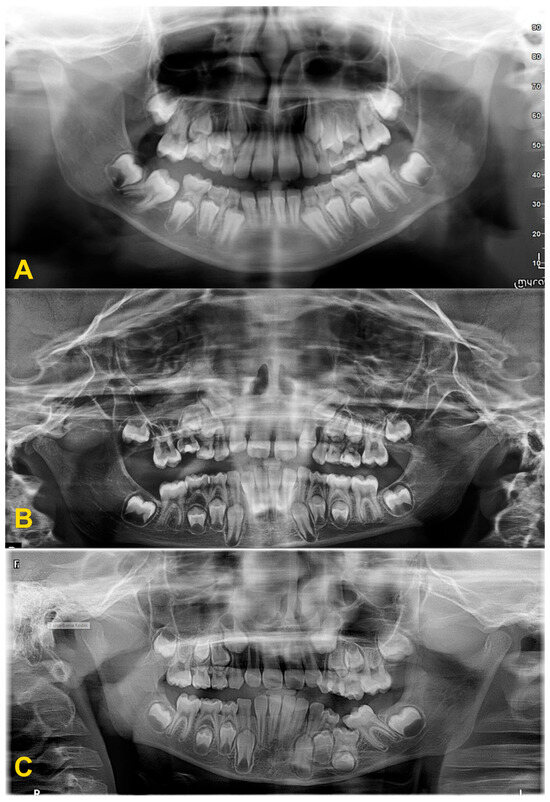

The diagnosis of tooth infraocclusion is multifaceted, involving a combination of detailed medical history, clinical examination, and advanced imaging techniques. To extend the diagnosis and monitor the reinclusion process, radiological examinations (dental X-rays—Figure 2, panoramic X-rays—Figure 3, and cone-beam computed tomography (CBCT)—Figure 4), diagnostic models (Figure 5A,B), intraoral scans (Figure 5C,D), and dental photography (Figure 6, Figure 7, Figure 8, Figure 9 and Figure 10) are used.

Figure 3.

Panoramic X-ray examinations: (A) mild infraocclusion of tooth no. 55 (immersion of 1–2 mm); (B) moderate infraocclusion of tooth no. 55 (infraposition of 2–3 mm), displacement and growth delay of permanent successor, and angulation of the adjacent teeth with loss of space; and (C) severe infraocclusion of tooth no. 75 (immersion of more than 3 mm), displacement and growth delay of permanent successor, severe angulation of the adjacent teeth with loss of space (the same patient as in Figure 6C).

Disorders of the occlusal plane and displacement of the adjacent teeth: (A,B) panoramic X-rays—displacement of the adjacent teeth, bone defect and growth delay of the permanent successor due to the severe infraocclusion of tooth no. 75 before (A) and after the extraction of tooth no. 75 (B). Surgery was performed under general anesthesia with simultaneous extraction of teeth nos. 38 and 48 due to crowding. Lack of space for tooth no. 35, improvement of root development and position of tooth no. 35; (C,D) intraoral photography (another patient)—displacement of the adjacent teeth, disturbance of the occlusal plane with lateral open bite, and bone defect—situation after too-late removal of reincluded teeth with lack of permanent successors, (E) panoramic X-ray—moderate infraocclusion of tooth no. 65, displacement of the tooth no. 25 in relation to its antimere, incorrect position of the tooth no. 23 with suspected cyst, moderate infraocclusion of teeth nos. 74, 84, and 85, no resorption of the mesial root of tooth no. 85, mild infraocclusion of tooth no. 75.